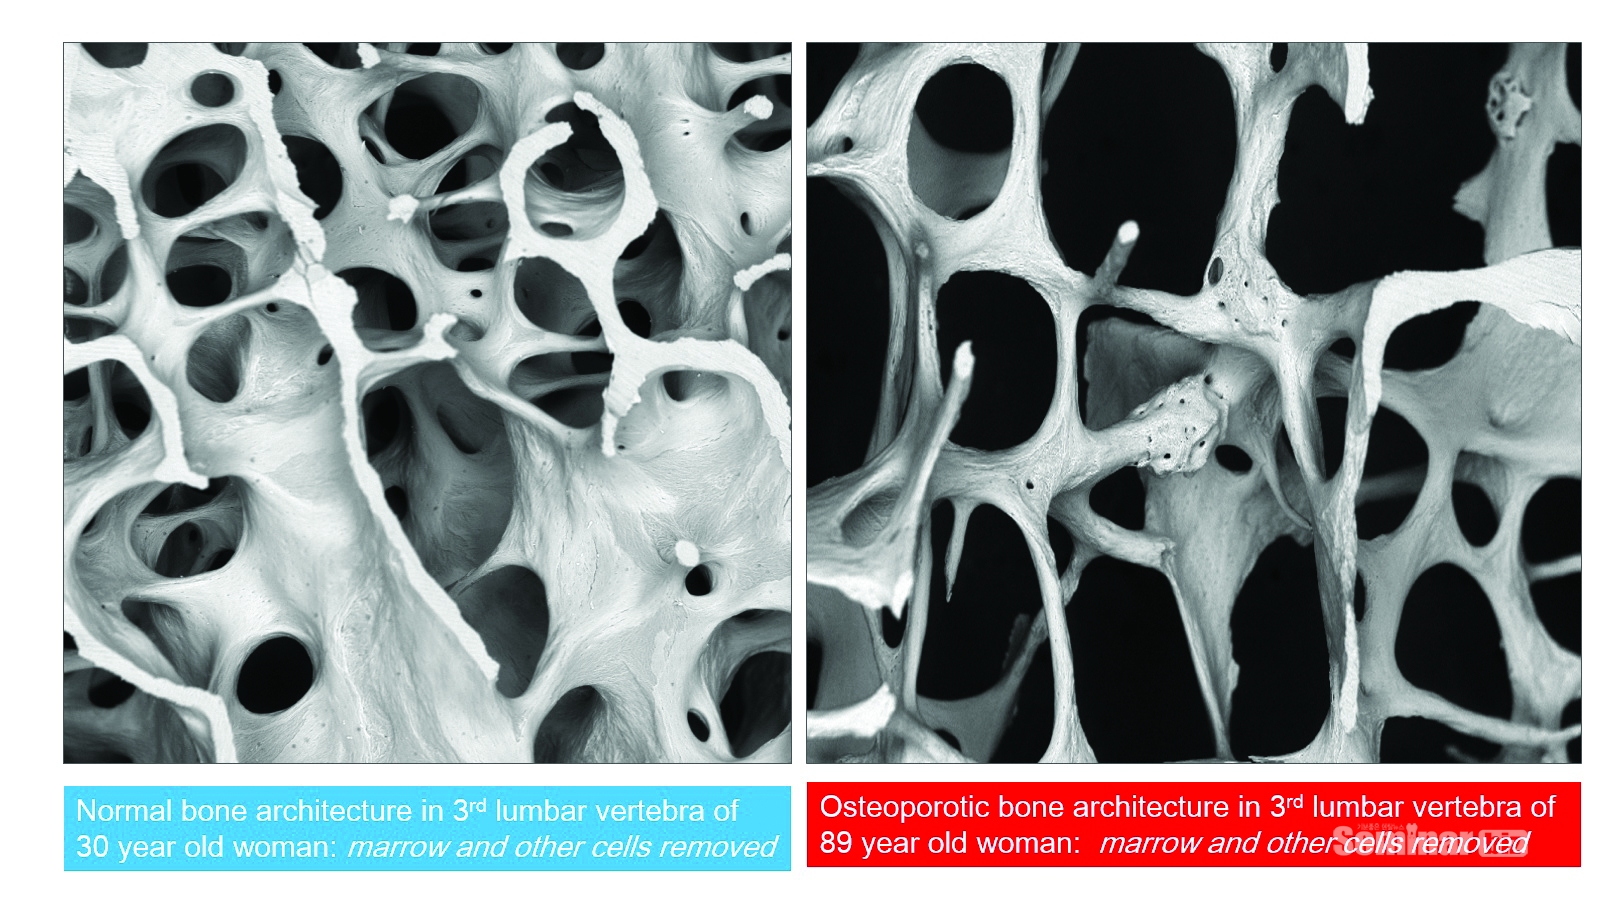

골다공증은 뼈에서 미네랄(칼슘아파타이트)량이 감소되고 뼈의 미세구조가 와해되어 뼈가 약해져서 골절의 위험이 증가하는 질환으로 정의하고 골다공증의 진단은 골밀도측정기로 골밀도를 측정해서 World Health Organization(WHO)의 가이드라인에 따라 T-score가 -2.5 이하인 경우를 골다공증이라고 진단하여 왔다.

그래서 최근에는 골다공증은 뼈를 만드는 활동과 흡수·소실시키는 과정의 불균형에서 비롯된다라고 언급하고 있다. 특히 골수의 기능 부전으로 발생되기 때문에 이러한 불균형 현상이 국소적으로 나타나기도 하고 전신에 걸쳐서 나타나기 때문에 각 골격계마다 진단과 치료가 다양화 되어야 한다(Figure 4-1).

결국 골다공증은 골수내부에서 발생되는 기능부전으로 인한 골흡수와 재형성의 불균형 가장 흔한 대사성 골질환으로서, 우리나라 50세 이상 남성 12%, 여성 33%, 세계적으로 2억 명 이상에게 발병한다고 알려져 있다.